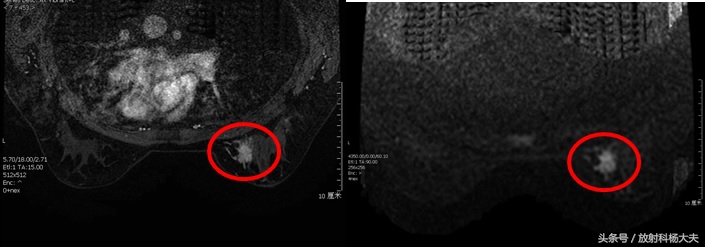

上图同一患者,MR发现乳腺癌,BI-RADS 4类

这个患者的MR做完后,在右侧乳腺内发现了异常的强化,但这种强化,按照BI-RADS分类来说,算是III级(IV级需要活检,V级是恶性)。